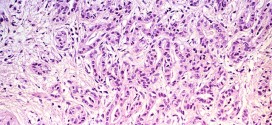

El carcinoma viliforme de la cavidad oral. Durante los primeros años de vida de una persona, las células normales se dividen más rápidamente para permitir el crecimiento. El cuerpo está compuesto por billones de células vivas. Las células normales del cuerpo crecen, se dividen formando nuevas células y mueren de manera ordenada. Una vez que se llega a la edad …